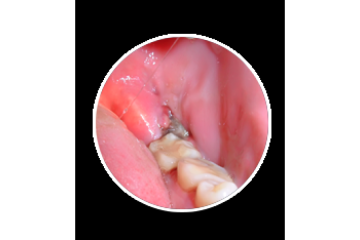

How Wisdom Teeth Infection Removal Helps Pain Fast

Wisdom Teeth Infection Removal provides fast and effective relief from pain, swelling, and dental infections. Get safe treatment from experienced dentists using advanced methods. Our affordable and premium care ensures quick healing and comfort. Choose Wisdom Teeth Infection Removal for reliable, same day dental services and restore your oral health with exp...